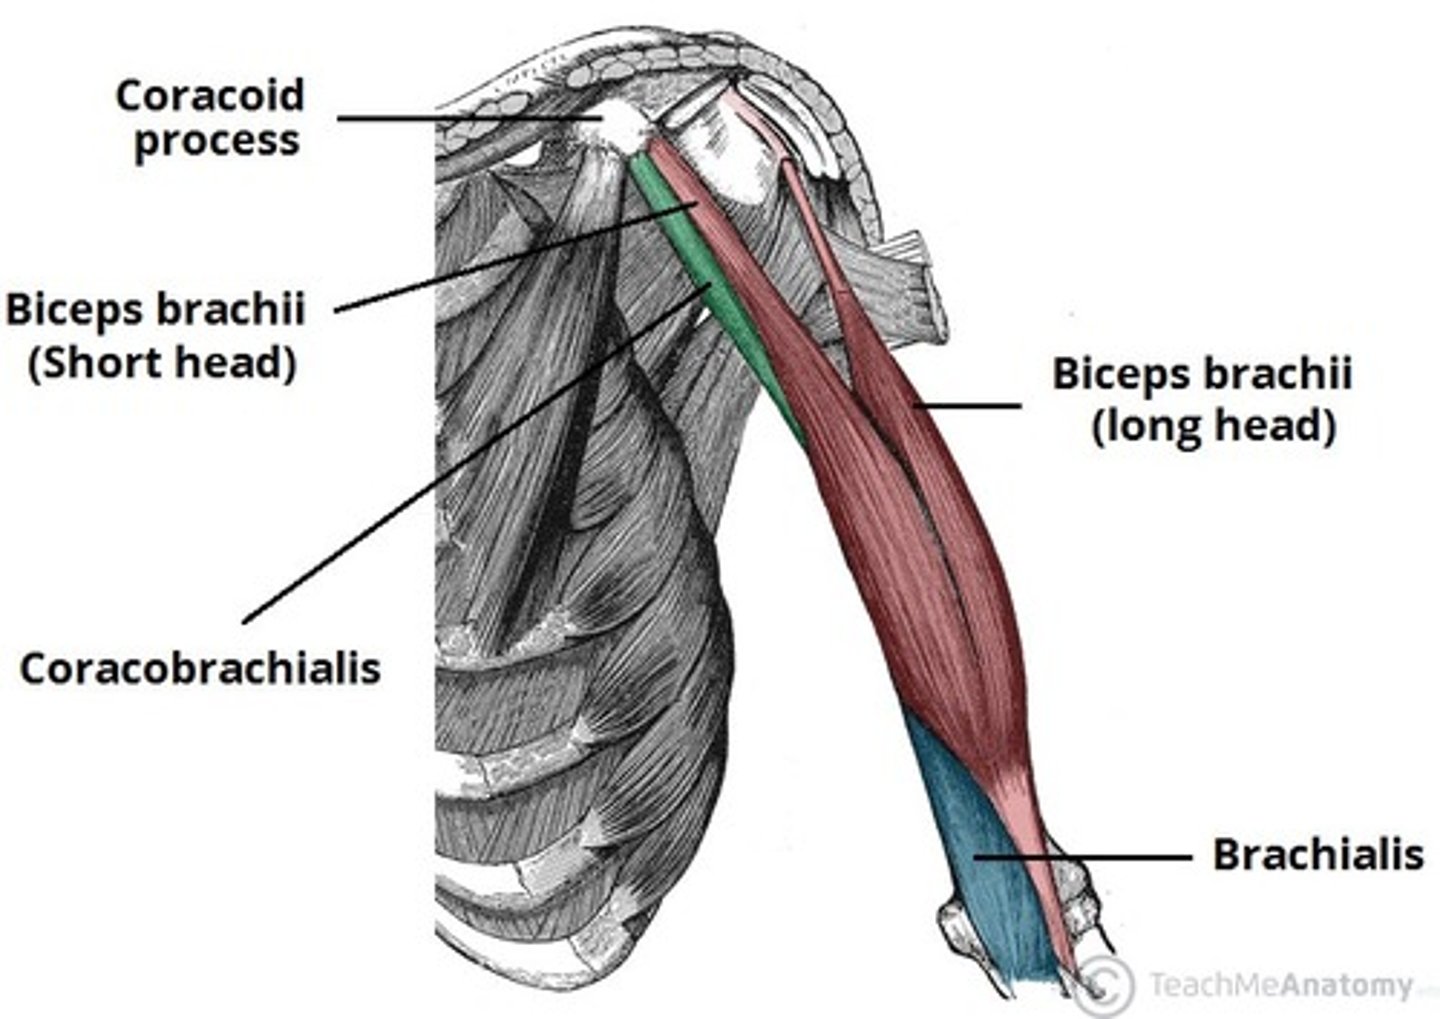

(Muscles of the arm:) Anterior compartment (flexor)

•Biceps brachii

•Brachialis

•Coracobrachialis

(Anterior compartment (flexor):) Biceps brachii

-Flexes and supinates forearm

-Musculocutaneous n. (C5 - C7)

-Bicipital aponeurosis: membranous band running from the biceps tendon across the cubital fossa and merges with antebrachial deep fascia. It is superficial to and protects the brachial a. and median n.

(Anterior compartment (flexor):) Brachialis

-Flexes forearm

-Musculocutaneous n. (C5 – C7)

-Deep to biceps brachii m. and is the main flexor of the forearm

(Anterior compartment (flexor):) Coracobrachialis

-Flexes and adducts the arm

-Musculocutaneous n. (C5 - C7)

-Pierced by the musculocutaneous n. and located in the superomedial part of arm